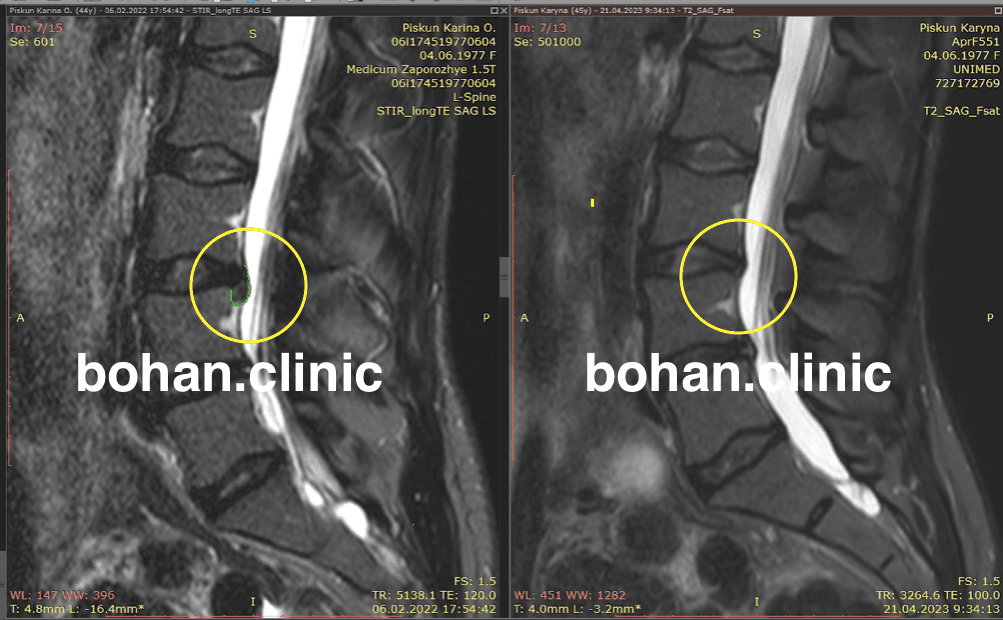

Метод лікування грижі шляхом стимуляції резорбції в Україні був впроваджений у 2020-2021 роках.  Алгоритм оцінки грижі на предмет резорбції, що використовується у клініках – є авторським, розроблений лікарем Боханом А.Ю.